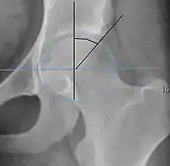

The most useful lines and angles that can be drawn in the pediatric pelvis assessing hip dysplasia are as follows:[3]

- (A) Hilgenreiner line, connects the inferior tips of the iliac bones,[4] at the triradiate cartilage. This line is used to measure the acetabular angle and as a reference for Perkin line.

- (B) Perkin line is perpendicular to Hilgenreiner line, touching the lateral margin of the acetabular roof.[5] This leads to four quadrants and a normal femoral head has to be located in the inferomedial quadrant. We can measure the lateral displacement of the femoral head with regard to the Perkin line by dividing the width of the head that crosses the Perkin line by the diameter of the head. The value for patients under 3 years must be 0 and in older children this ranges from 0 to 22%.